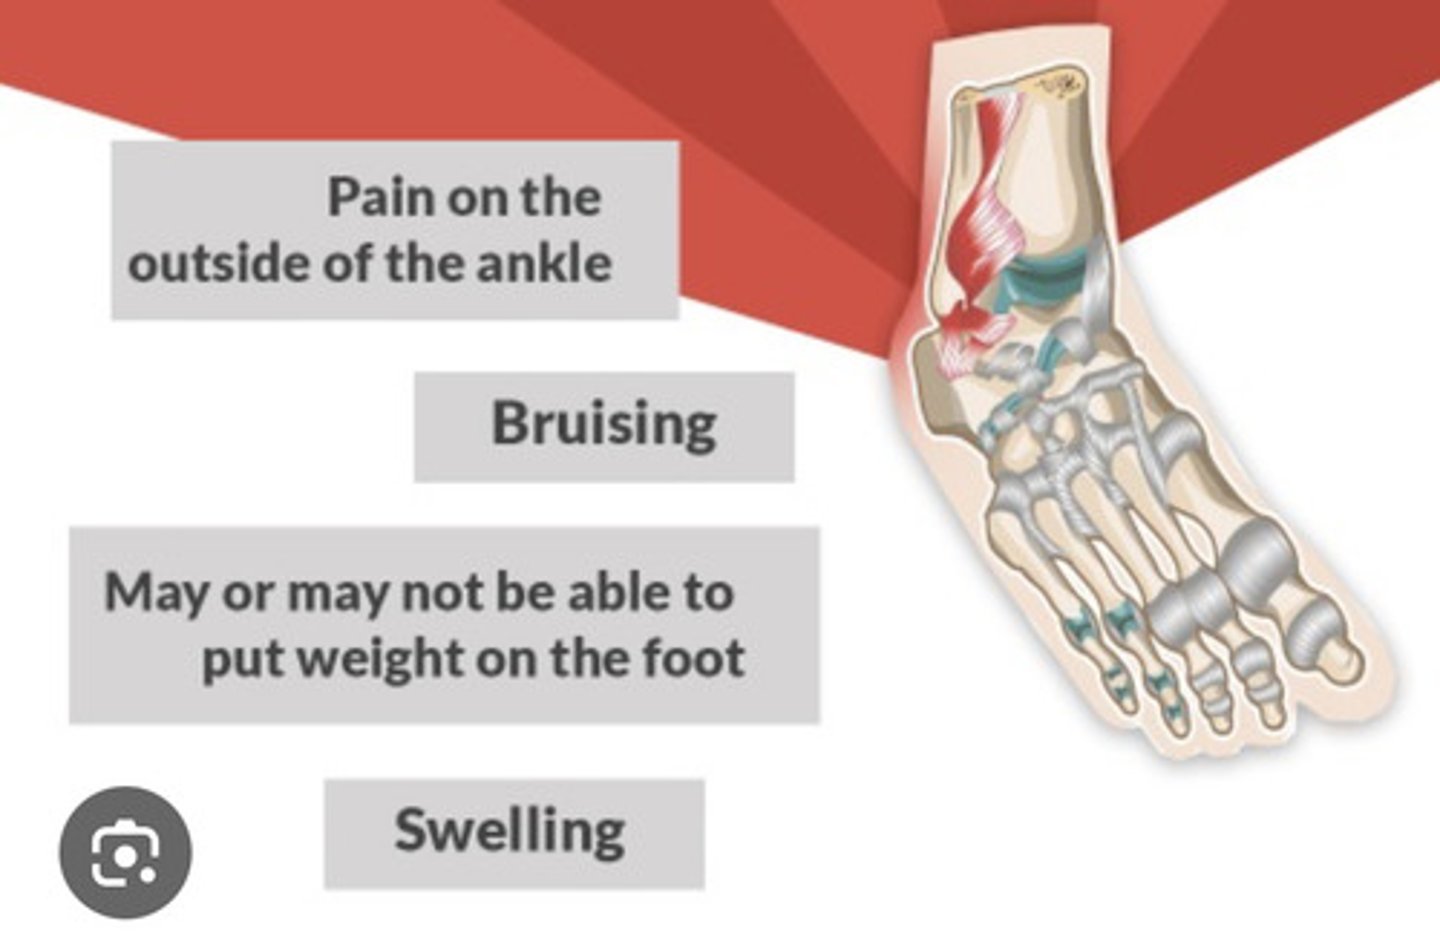

What is a SPRAIN

- mechanical overload of a joint

=> ligament injury = stretch, tear (complete or incomplete), assess for associated bone injury

- common sprains: ankle (inversion); knee (ACL & MCL); elbow; wrist or ligament tear (eg. ACL tear - more dysfunctional)

What are the s&s in a sprain

- pain, inflammation

- contusion (bruise)

- decreased function